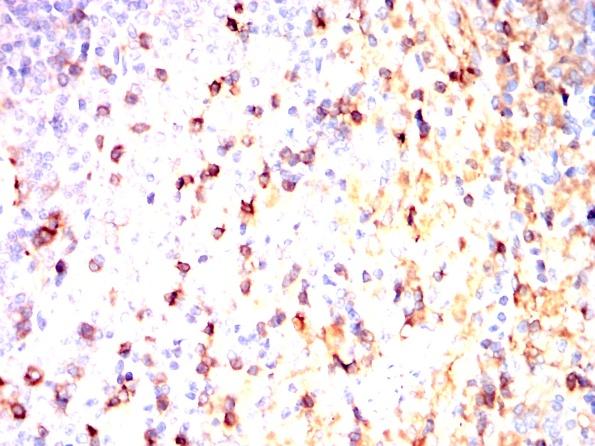

利用THY1小鼠单抗结合DAB染色对石蜡包埋大鼠脾脏进行免疫组化分析。 |